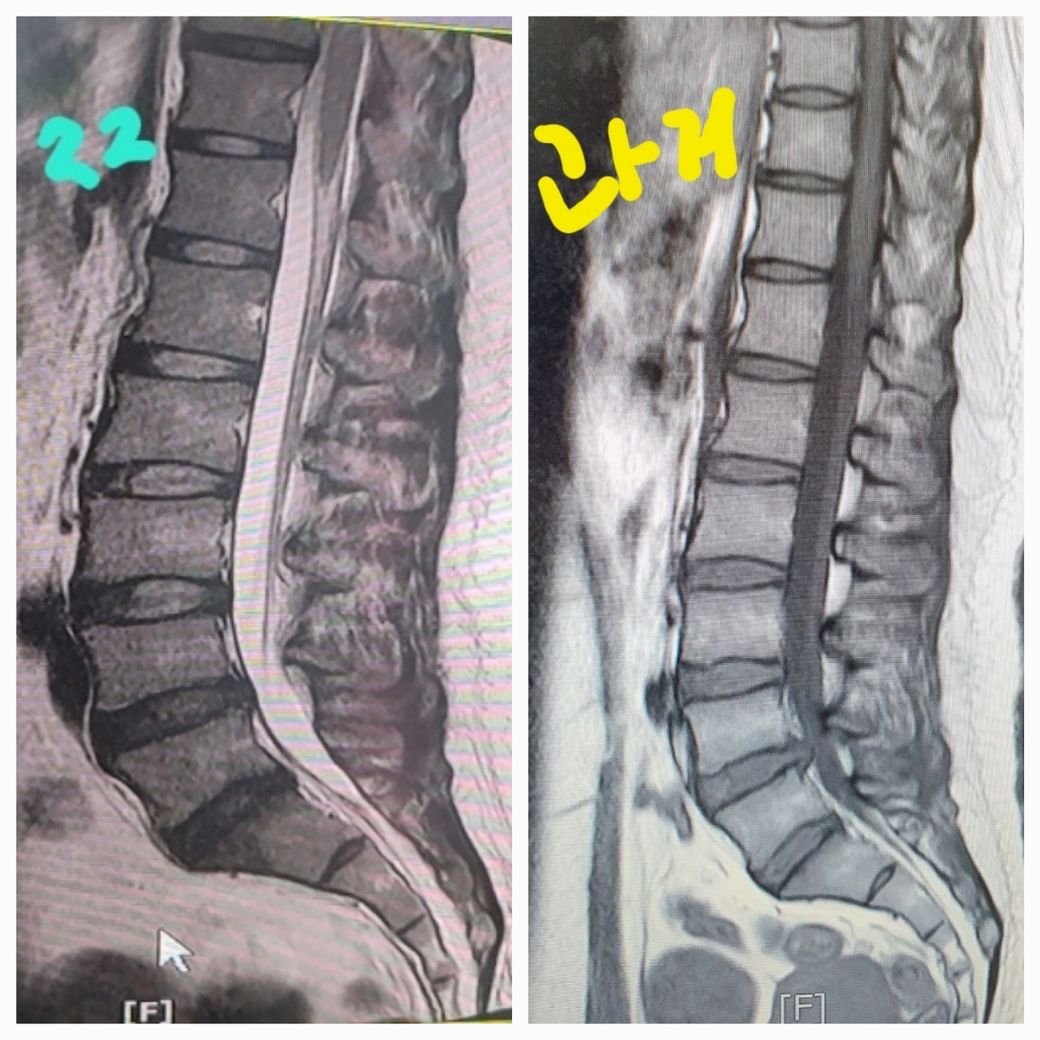

과거와 현재의 허리상태 비교분석 궁금합니다

과거와 현재 허리상태 비교분석드립니다.

교통사고후 연관성여부도 분석드려요.

중간허리가 너무아파요

과거에비해 현재상태 판독지도 더 안좋게나와 걱정입니다.

또한 허리 MRI는 해당 1컷의 사진만으로는 충분한 판독이 어려우며 전반적으로 현재의 허리 상태가 과거보다는 악화된 상태라는 것은 확인이 가능합니다.

첨부하신 영상의 이미지 종류가 달라서 평가가 불가능합니다.

보시면 하얗게 보이는거랑 검게 보이는게 서로 다르게 나와서 알수가 없어요.

단편적인 사진만으로는 정확한 비교가 어렵습니다. 다만 4-5번 디스크가 이전에 비해서 후방으로 더 튀어나온 것으로 보입니다. 교통사고와의 연관성은 이 사진만으로는 알기 어렵고 현재 진료를 보고있는 담당 의사분께서 판단할수 있습니다. 허리 디스크 환자의 경우 허리를 구부리는 자세는 디스크에 좋지 않습니다. 허리를 구부리거나 무거운 것을 드는 동작은 허리 디스크 후방으로 힘을 작용하게 되며 이는 디스크 돌출을 유발할수 있습니다. 치료는 물리 치료, 약물 치료, 신경 차단 주사 치료를 하실수 있겠습니다.